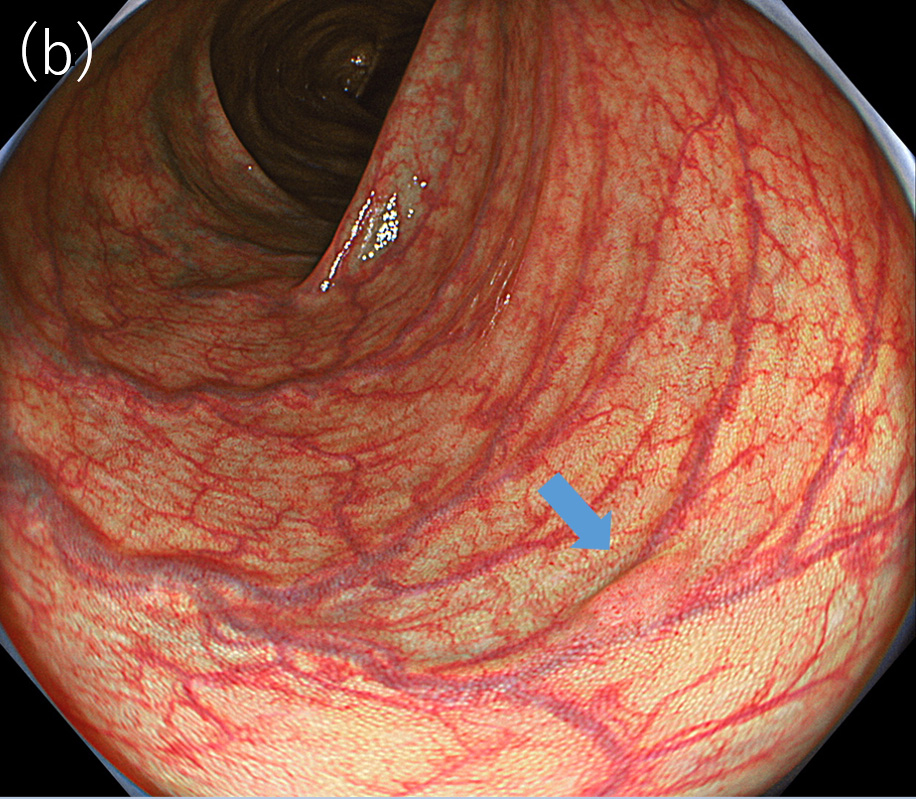

〈図1〉XZ1200による同一病変に対する中遠景観察像(a)白色光観察; (b)TXI観察(モード1)

〈図2〉 XZ1200による同一病変に対するNBI中遠景観察像(a)BAI-MAC OFF; (b)BAI-MAC ON